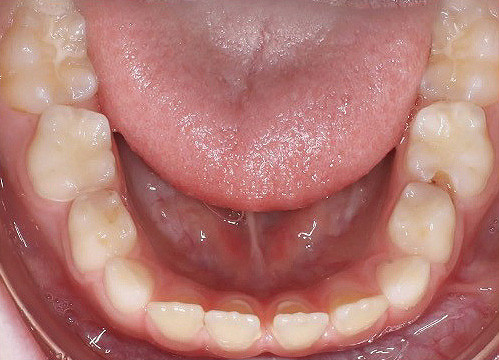

Klinisches Fallbeispiel 1 (Abb. 1a–u)

Neunjähriger Patient mit deutlich vergrößertem Overjet aufgrund eines Distalbisses in Kombination mit einer Protrusion der Oberkieferfront. Habits bzw. myofunktionelle Aspekte wurden adressiert. Die Behandlung erfolgte mit einem Invisalign-Schienensatz (56 Aligner) mit Precsion Wings im Rahmen einer Frühbehandlung zur Prophylaxe eines Frontzahntraumas.